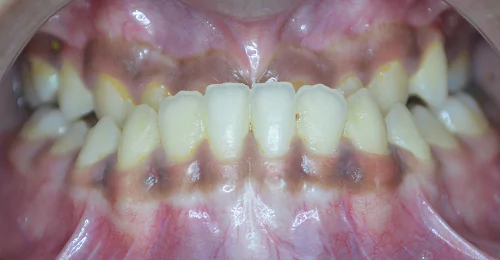

Orthodontic Case – I

(Case Done by Dr. Sonali Deshmukh M.D.S. / Orthodontist )

Anterior Crossbite Correction

Without Extraction Of Teeth

A young newly married female had crossbite in front teeth and when she smiled she felt her teeth appeared crooked. Being newly married she also had concerns regarding wearing braces. Assessing the situation, we advised ceramic braces and treated the condition without extracting or removing any teeth.

Pre Treatment

The treatment was completed successfully after a period of 18 months. Our patient is now embarked on her newly married life with more confidence.